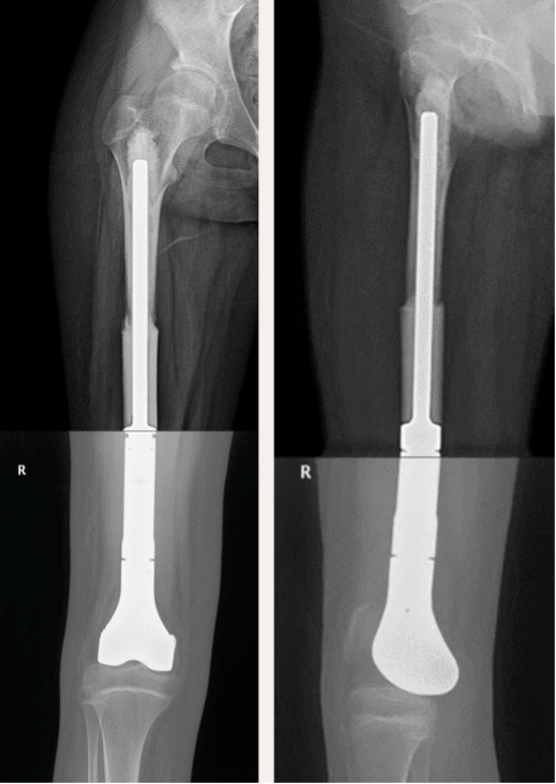

切除肿瘤后就需要进行保肢重建,这位病人只有12岁,骨骼还未发育完全,成人用的人工膝关节不适用于儿童。除了没有儿童特殊的小号尺寸,重建需要牺牲膝关节对侧的骨骺(生骨中心),儿童在发育时会产生双下肢不等长。所以我们根据患者下肢的CT数据建模,设计了可以保留胫骨侧骨骺的半膝关节假体,并3D打印订制个性化的膝关节假体。手术中将异体股骨干套接在假体插入杆,插入股骨残端髓腔内,通过填塞骨水泥固定。使用人工补片穿行假体内,与胫骨侧韧带残端缝合,重建膝关节周围的软组织稳定机制。

手术后患者恢复良好,佩戴膝关节支具伸直位固定2周后开始康复锻炼,并继续进行术后化疗6次后治愈结疗。

术后6个月患者已恢复膝关节正常功能,站立行走下蹲无障碍。能正常日常生活。

患者术后2年复查X线摄片图像,膝关节在位,异体骨已与股骨融合。